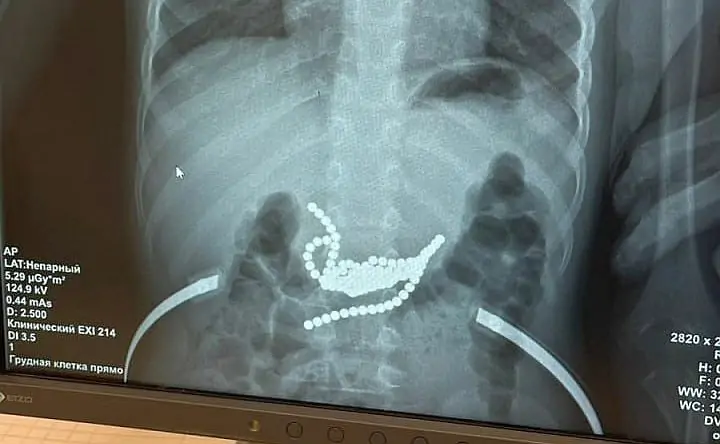

Ранее donnews.ru писал о том, как хирурги Ростовской областной детской клинической больницы достали из желудка мальчика 50 магнитных шариков. Как оказалось, родители купили мальчику магнитные шарики, чтобы играя в них, малыш развивал мелкую моторику, но ребёнок их съел.

Болевых или дискомфортных ощущений у ребёнка не было, родителям о случившемся он сказал между делом. После этого родители обратились к медикам.

Эндоскопическая попытка извлечь магнитные шарики оказалась безуспешной. И в итоге потребовалась очень полостная операция.

По словам одного из хирургов, который оперировал ребёнка, Антона Штарева, магнитные шарики были неодимовые, у них самая большая сила магнетизма.

«Основная часть магнитов находилась в желудке, другие — в тонкой кишке, поэтому, чтобы извлечь все магниты, пришлось вскрывать просвет и кишки, и желудка. В этом сложность и уникальность операции. Если бы родители обратились в больницу на пару часов позже, могла бы произойти перфорация, и тогда последствия для здоровья малыша были бы гораздо более тяжёлыми», — рассказал хирург.